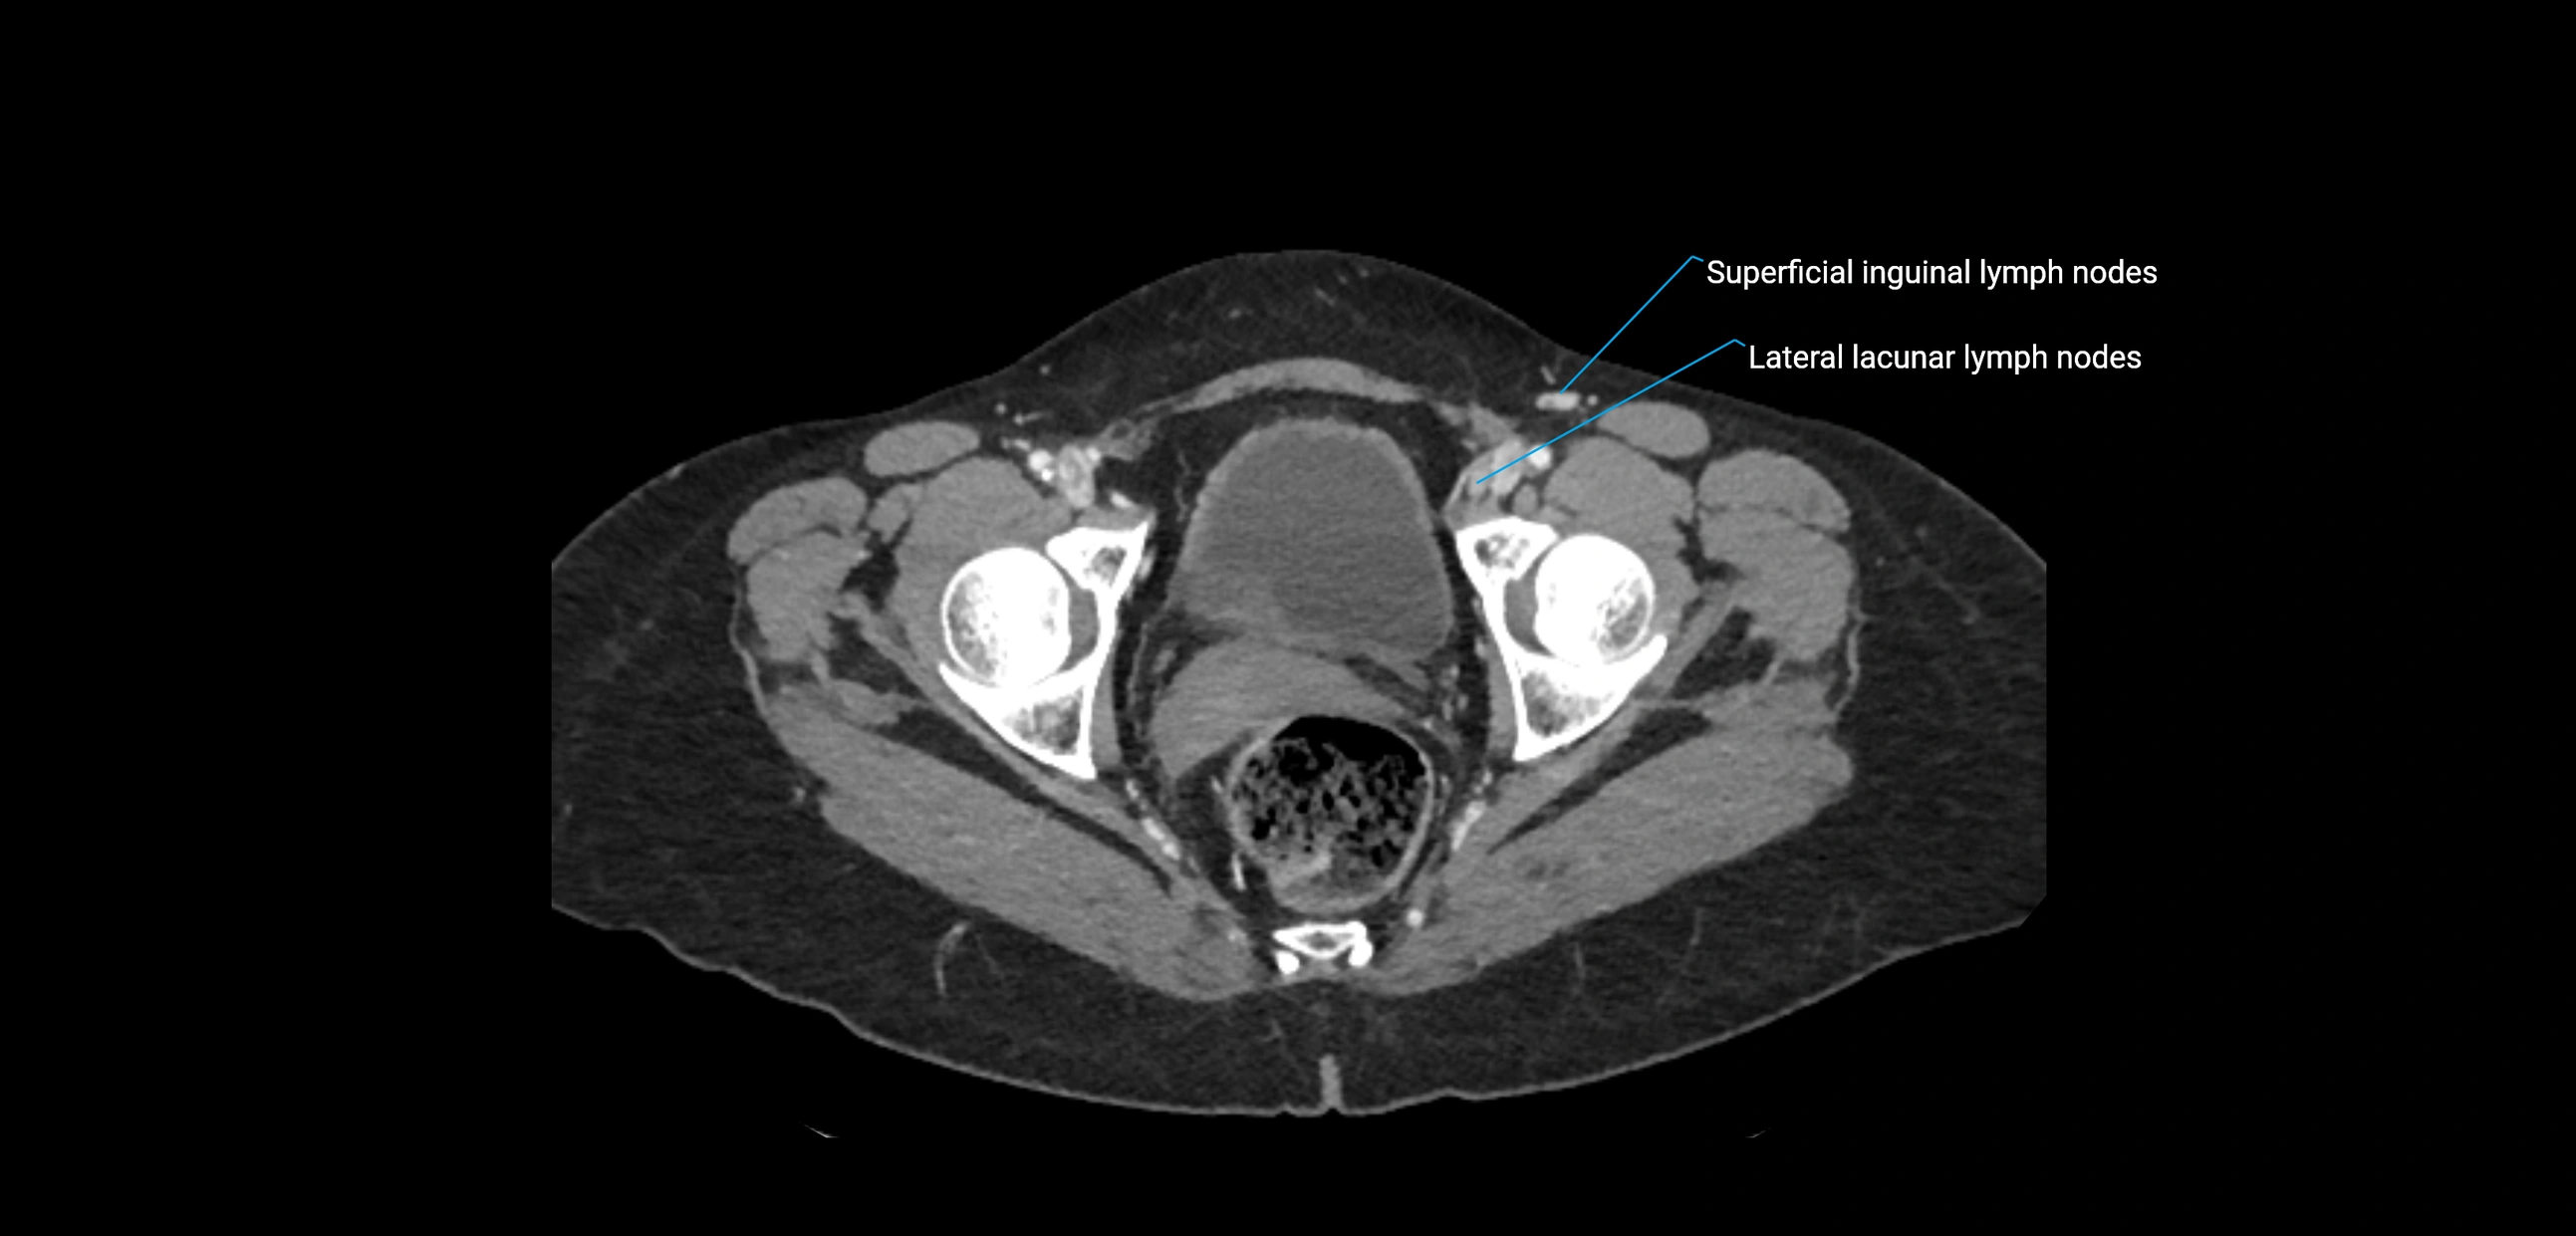

CT image

image